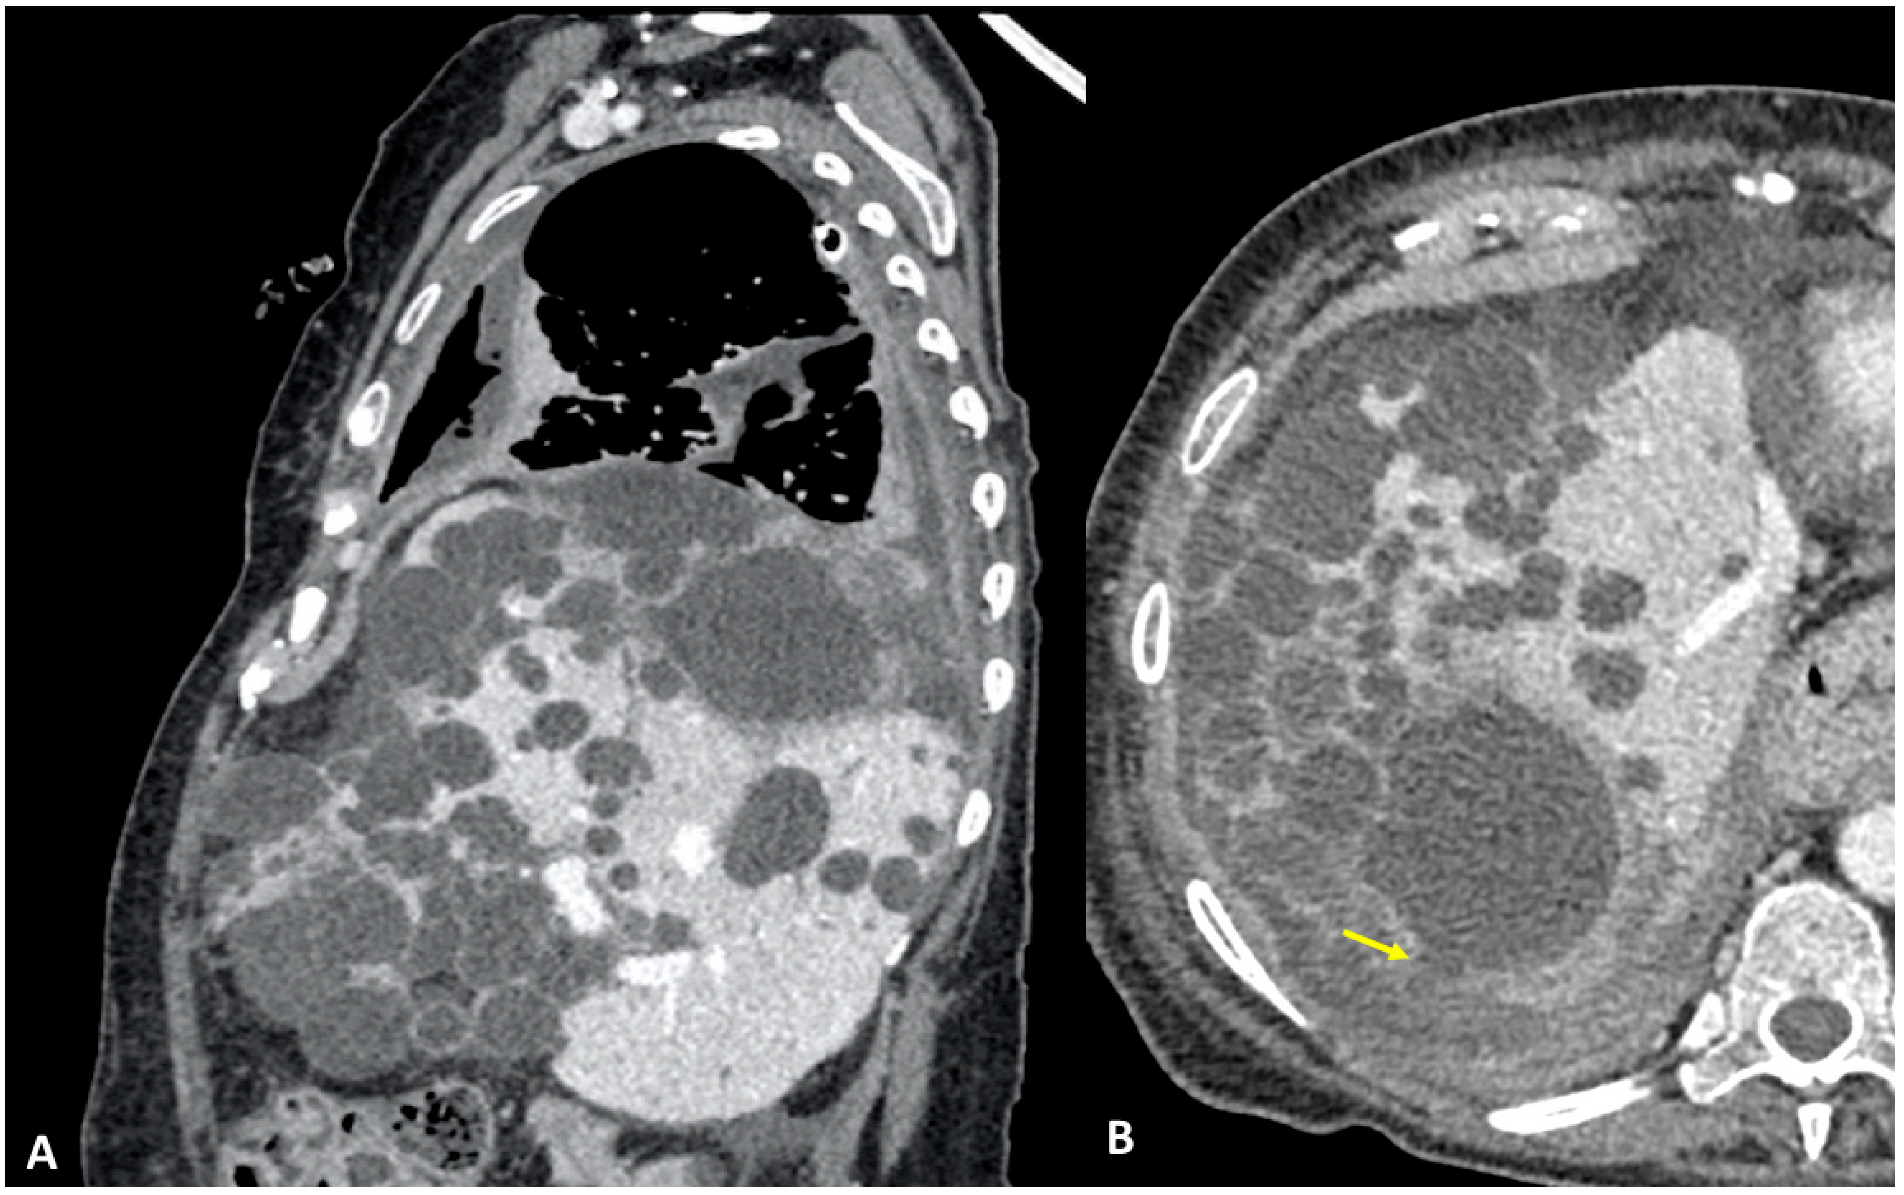

A 61-year-old woman was referred to our institution in an ER setting complaining of chest pain and dyspnea. She was affected by hepatic and renal polycystosis, she previously underwent right nephrectomy, and she had been on dialysis for the last 4 years for chronic renal failure. Physical examination revealed diminished breath sounds over the right hemithorax. Laboratory routine tests showed mild neutrophilia, increased CRP levels, and a slight increase in direct bilirubin and creatinine. She underwent a chest X-ray showing a right pneumothorax (PNX) that was drained. Consequently, the patient underwent contrast-enhanced thoracoabdominal. CT showed a right pneumothorax associated with enhanced pleural thickening. At the CT, the fluid component in the right lower lung lobe was inseparable from one of the right lobe hepatic lobe cysts (Figure 1A,B). Moreover, a focal defect was appreciable in the hepatic cyst and in the right hemidiaphragm that appeared in connection with the pleural fluid empyema. The CT findings were suggestive of HTF. The following day, MRCP was performed, which confirmed that one of the cysts, localized at the seventh hepatic segment, presented a focal wall discontinuity. MRCP further supported the hypothesis of a direct connection between the hepatic cyst and the pleural cavity, but did not identified the fistulous tract (Figure 2A,B).

Figure 1.

(A,B) Contrast-enhanced CT, sagittal planes (A), and axial planes (B) showing right empyema and pleural thickening with enhanced pleural leaflets. In both figures (A,B), the right lower lung lobe and a hepatic cyst look strongly adjacent (arrow), without a definite fistulous tract.